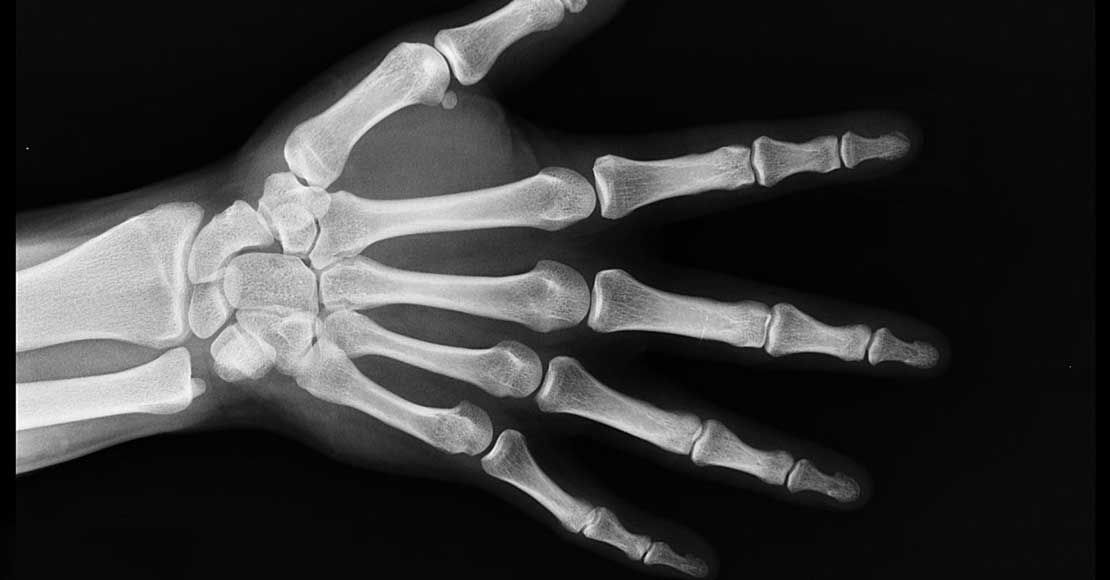

Upadek podczas jazdy na nartach, intensywna gra w siatkówkę, koszykówkę oraz wiele innych aktywności fizycznych wiąże się dużym ryzykiem wybicia, zwichnięcia lub złamania palca. Sposób leczenie i rehabilitacji lekarz dobiera w zależności od rodzaju i stopnia urazu. Maksymalne usztywnienie zapewniałoby włożenie ręki w gips – trzeba jednak pamiętać, że to rozwiązanie wyjątkowo mało komfortowe. Choćby z uwagi na ciężar masywnego opatrunku czy trudności z zachowaniem higieny osobistej. Dlatego jeśli tylko gips nie okaże się absolutnie konieczny, warto poszukać alternatywnej metody stabilizacji. Orteza na palec nada się w takich przypadkach idealnie. Zgodnie ze słowami przedstawicieli firmy Mega Medic: tego rodzaju sprzęt daje możliwość usztywnienia wyłącznie kontuzjowanej części ciała, dzięki czemu nie ma konieczności unieruchamiania całej ręki. Kolejną dużą zaletą specjalistycznych stabilizatorów będzie wysoki stopień elastyczności, co pozwala łatwo dopasować je do indywidualnej budowy anatomicznej.